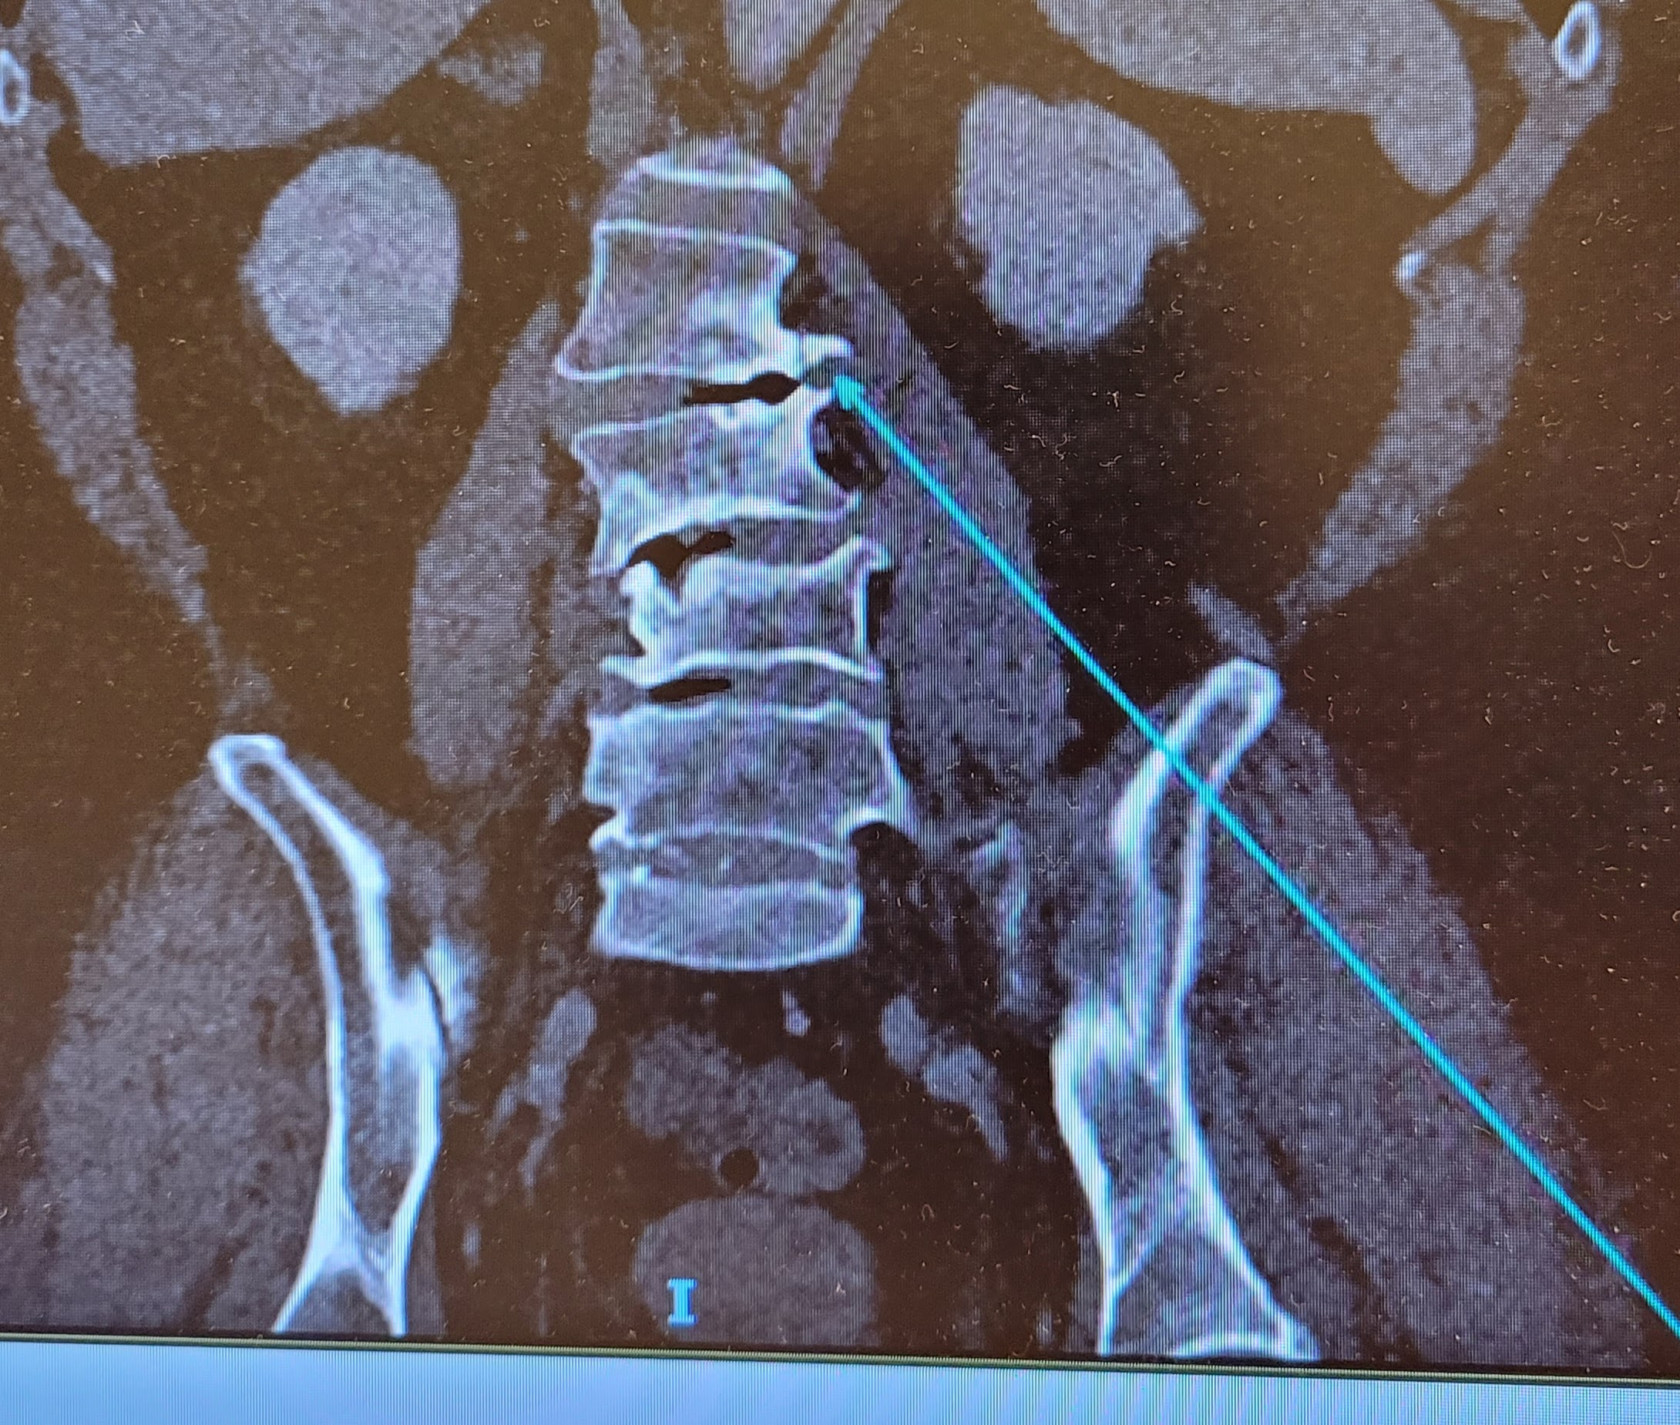

Eergisteren had ik het consult bij de neuroloog en inderdaad is dat de conclusie: alleen een operatie kan de pijnklachten verlichten. De MRI laat weinig verschil zien t.o.v. die van 10 maanden terug (zie hieronder), maar die wordt liggend gemaakt en ik ervaar juist toenemende klachten als ik sta en loop. Operatie moet wel in een ander ziekenhuis omdat dit soort complexe operaties niet in het AVL worden uitgevoerd. Ik zie hier tegenop, maar zo doorgaan kan ook niet. Ik ga steeds krommer lopen, er wordt een steeds groter deel van de huid van mijn been gevoelloos en heb ik zenuwpijn zodra ik ga staan of lopen.